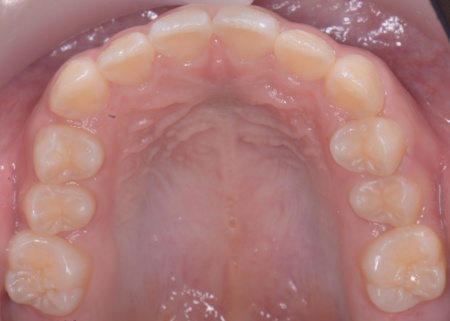

最後に、歯並びが整って見た目や噛み合わせにも問題がないことを確認し、装置を取り外して第1期矯正治療を終了しました。

現在も経過観察を継続していますが、歯が元の位置に戻る後戻りも見られず、残っている乳歯から永久歯への生え変わりも順調に進んでいます。